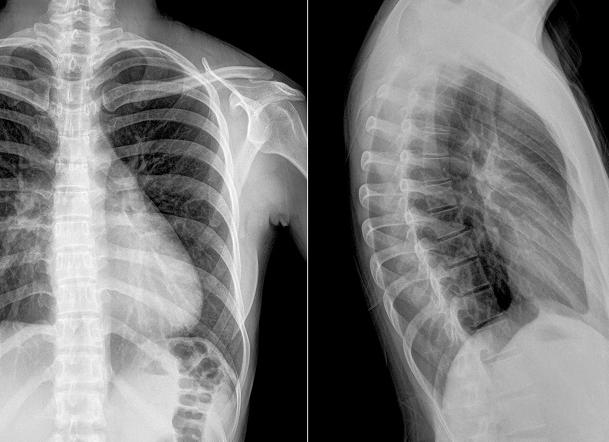

Как правило, для того, чтобы избежать затенения органами брюшной полости и получить информативный снимок, делают рентген грудного отдела позвоночника в двух проекциях: прямой и боковой. Для получения снимка в прямой проекции пациент ложиться на спину без подушки, ноги прямые, руки – вдоль туловища. Иногда применимо вертикальное положение обследуемого (стоя). Когда необходима рентгенограмма в боковой проекции, требуется лечь на бок. Опорную руку обследуемый подкладывает под голову, второй рукой обхватывает колени (ноги слегка согнуты).

Снимок следует делать минимум в двух проекциях. Это нужно, потому что исследуют трёхмерный объект, а рентгеновский снимок – плоский, двухмерный. Нахождение определённой патологии можно заметить именно в этих проекциях.

Для получения наиболее объективной картины состояния грудного отдела, рентгенографию делают в прямой и боковой проекциях. В первой ситуации больному нужно лежать на спине без подушки. Ноги следует полностью выпрямить, руки положить вдоль тела. Может быть такое, что обзорный снимок (в прямой проекции) делают, когда пациент находится в положении стоя.

Чтобы сделать рентген в боковой проекции, обследуемый должен лечь набок. Руку, которая прилегает к столу, ему требуется поднять вверх и положить под голову. Второй рукой нужно обхватить колени, перед этим несильно согнув их. Когда делают снимок, следует лежать, не дыша и делать всё, что скажет доктор.

Рентген грудного отдела производится лежа на спине и на боку. Диагностику проводят обычно в двух проекциях ─ прямой и боковой. Гораздо реже доктору для полной картины требуются снимки под углом в 45°. Также возможна рентгенография с использованием функциональных проб: пациент лежит на боку, ему предлагают осуществлять сгибание и разгибание. В связи с тем, что грудной отдел позвоночного столба не такой подвижный как остальные, функциональные пробы используются редко, а если используются ─ подбираются врачом индивидуально.

Рентген позвоночника назначается в обязательном порядке при диагностике таких тяжелых повреждений, как переломы. Благодаря рентгену удается определить точное местоположение костных отломков и исходя из этого выбрать способ репозиции. Рентгенологическое исследование обладает высокой информативностью при оценке степени и характера смещения позвонков относительно друг друга, поэтому его применяют при обследовании всех видов искривления позвоночного столба. Костные, хрящевые и мягкие ткани имеют различную плотность, поэтому по-разному отображаются на рентгеновском снимке. Это позволяет включить в сферу применения рентгена диагностику заболеваний суставов, в том числе образования хрящевых тел в суставной жидкости. Часто именно рентген позволяет обнаружить опухоли в районе позвоночника. Само по себе исследование говорит только о наличии опухоли, для того чтобы точно определить ее природу, применяется биопсия. Чтобы рентгенологическое исследование было более достоверным, оно проводится в 2 проекциях: боковой и задней.